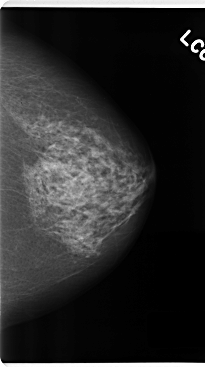

C_0224_1.LEFT_CC

LEFT_CC LINES 4768 PIXELS_PER_LINE 2656 BITS_PER_PIXEL 12 RESOLUTION 50 NON_OVERLAY